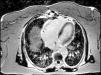

Considering the patient's ischemic burden, new-onset biventricular systolic dysfunction, and the absence of signs of pulmonary embolism, and as she was clinically stable after three days, it was decided to perform cardiac magnetic resonance imaging (MRI), which showed slight left ventricular systolic dysfunction, right ventricular dilatation with severe systolic dysfunction and transmural late enhancement in the mid-apical segments of the right ventricle, highly suggestive of RVI (Figures 3 and 4). Pulmonary artery angiography showed no signs of pulmonary thromboembolism. In this non-linear clinical case cardiac MRI was sufficiently informative to enable a diagnosis to be made: RVI.

The patient's clinical deterioration with acute decompensated heart failure in spite of therapy, including revascularization, fluid resuscitation and inotropic support, was a warning that further investigation was required. Cardiac MRI provided a more conclusive study of ventricular function and wall motion abnormalities, and gadolinium late enhancement demonstrated that the ischemic region was in the right apical ventricular wall. Cardiac MRI is the most sensitive method to assess right ventricular function. Right ventricular involvement usually occurs in the inferior segments and the apex of the right ventricle, regions in which imaging of wall motion abnormalities with echocardiography is particularly challenging.8 Most reports do not specify an optimal timing for MRI in an acute setting, and each situation calls for different timings.